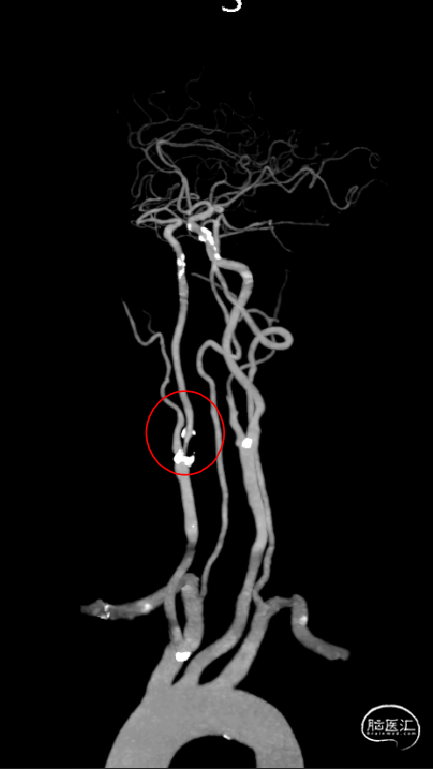

CTA提示:右侧颈内动脉起始部重度狭窄。

以260cm泥鳅导丝辅助125cm Simmons 2和6F导引导管超选右侧颈总动脉远端,撤出泥鳅导丝及造影管,再次造影可见右侧颈内动脉起始部重度狭窄,狭窄率约80%。